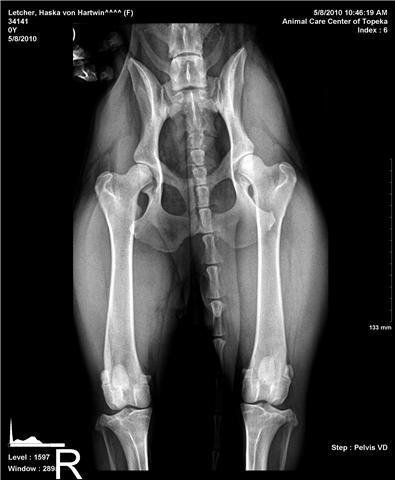

骨質疏鬆症不是時髦的疾病,

只是這種以往沒被 發現的病症,

在X光廣泛被運用在醫學攝影上後,

使得這種毛病無所遁 形,

因而受到重視,

患有骨質疏鬆症者,

從X光片 中,

很容易可以看出骨質出現很多的小孔洞。

然而根據專家研究,

骨質疏鬆症骨頭的

組成比率並沒有明顯的改變,

只不過是骨量全體變得比原先要少。